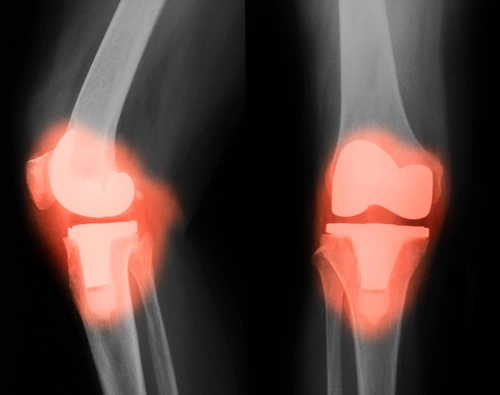

Απεικονιστικά, οι απλές ακτινογραφίες της πάσχουσας άρθρωσης είναι συνήθως αρκετές και μας δείχνουν μείωση του μεσάθριου διαστήματος, οστεόφυτα (οστικές προεξοχές), κύστες και σκλήρυνση του υποχόνδριου ιστού. Σπάνια θα χρειαστούν άλλες απεικονιστικές εξετάσεις, όπως αξονική ή μαγνητική τομογραφία της πάσχουσας άρθρωσης.

Τεχνητές αρθρώσεις με μεγάλη διάρκεια στον χρόνο

Οταν ο ασθενής παρουσιάζει κάποιο ή περισσότερα από τα παραπάνω προβλήματα, και έχει αναγκαστεί να αλλάξει τις καθημερινές του συνήθειες, τότε η χειρουργική αντικατάσταση της πάσχουσας άρθρωσης είναι η μόνη λύση. Με τις καινούργιες χειρουργικές τεχνικές, όπως είναι η αρθροπλαστική με ψηφιακή υποβοήθηση, MIS (minimal invasive surgery-τεχνική ελάχιστης επεμβατικότητας), οι ορθοπαιδικοί χειρουργοί έχουν καταφέρει να μειώσουν τον χρόνο παραμονής στο νοσοκομείο (1-2 ημέρες) και να εξασφαλίσουν για τον πάσχοντα ταχύτερη και πιο ανώδυνη αποκατάσταση, χωρίς όμως να παραγνωρίζουν το σημαντικότερο, δηλαδή τη δημιουργία μίας τεχνητής άρθρωσης η οποία θα διαρκέσει όσο το δυνατόν περισσότερα χρόνια!